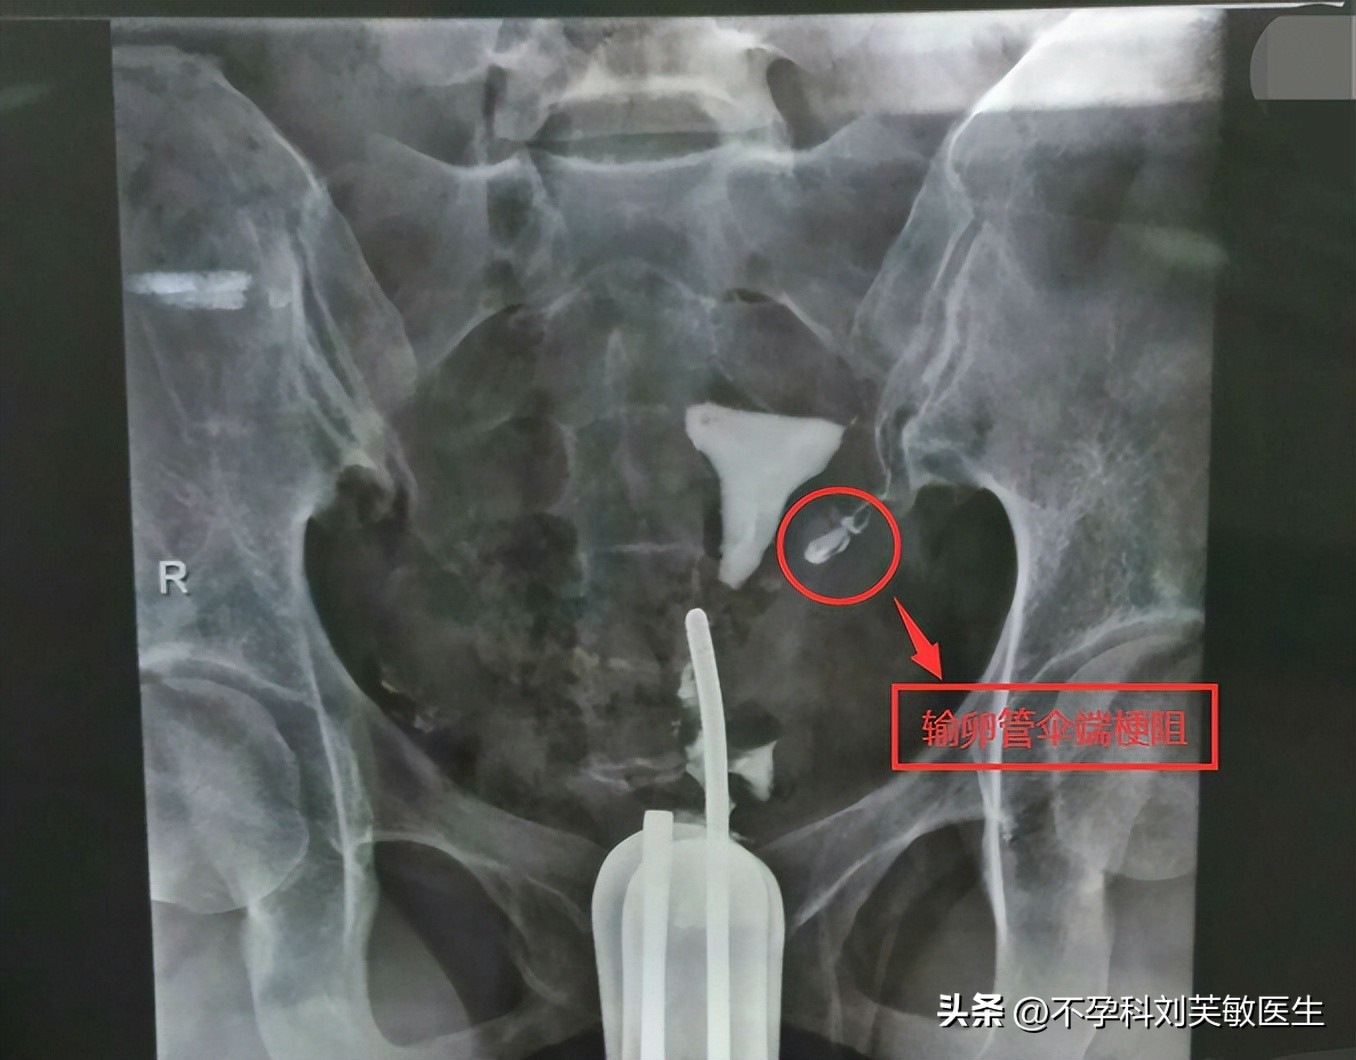

2.输卵管阻塞

输卵管不显影为角部阻塞;

只显影一段为狭部阻塞;

显影至远端,但造影剂清楚成片,第二片见造影剂点片状仍清楚,盆腔内无造影剂影,为伞部阻塞。

如果盆腔有造影剂涂抹,说明至少一侧输卵管是通的。如果双侧不通,可根据医生建议考虑手术治疗。